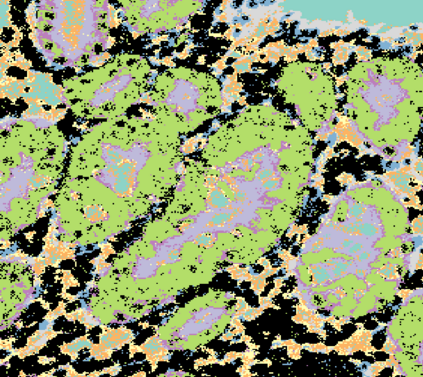

The usage of chemical imaging technologies is becoming a routine accompaniment to traditional methods in pathology. Significant technological advances have developed these next generation techniques to provide rich, spatially resolved, multidimensional chemical images. The rise of digital pathology has significantly enhanced the synergy of these imaging modalities with optical microscopy and immunohistochemistry, enhancing our understanding of the biological mechanisms and progression of diseases. Techniques such as imaging mass cytometry provide labelled multidimensional (multiplex) images of specific components used in conjunction with digital pathology techniques. These powerful techniques generate a wealth of high dimensional data that create significant challenges in data analysis. Unsupervised methods such as clustering are an attractive way to analyse these data, however, they require the selection of parameters such as the number of clusters. Here we propose a methodology to estimate the number of clusters in an automatic data-driven manner using a deep sparse autoencoder to embed the data into a lower dimensional space. We compute the density of regions in the embedded space, the majority of which are empty, enabling the high density regions to be detected as outliers and provide an estimate for the number of clusters. This framework provides a fully unsupervised and data-driven method to analyse multidimensional data. In this work we demonstrate our method using 45 multiplex imaging mass cytometry datasets. Moreover, our model is trained using only one of the datasets and the learned embedding is applied to the remaining 44 images providing an efficient process for data analysis. Finally, we demonstrate the high computational efficiency of our method which is two orders of magnitude faster than estimating via computing the sum squared distances as a function of cluster number.